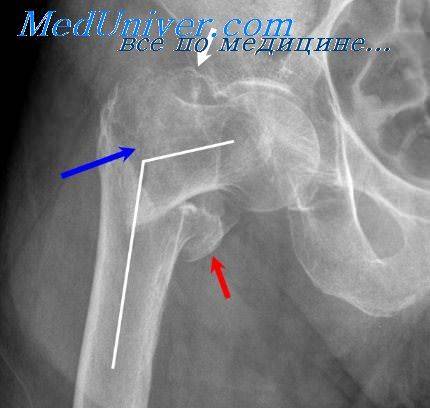

У людей пожилого и старческого возраста на фоне сенильного остеопороза переломы возникают при сравнительно небольшой травме. В основпом это переломы шейки бедренной кости и вертельной области, хирургической шейки плечевой кости, позвоночника, предплечья в типичном месте и некоторые другие. Из-за хрупкости костей переломы, как правило, оскольчатые, края отломков заостренные, что способствует рапепию сосудов и развитию кроветечений в зоне перелома.

Оглавление темы «Переломы костей. Рентгенологические признаки переломов»:1. Дистальная и проксимальная эктромелии. Патология пальцев и конечностей2. Нарушение количества пальцев. Расщепление кисти и синдактилия3. Симфалангия и патология стопы. Множественные пороки скелета4. Травмы скелета. Переломы костей скелета5. Переломы трубчатых костей. Возрастные особенности переломов6. Вторичное заживление костей. Осложненные переломы7. Огнестрельные переломы. Патологические переломы8. Патологическое заживление переломов. Ложный сустав — псевдоартроз9. Переломы пояса верхней конечности. Переломы костей верхних конечностей10. Переломы костей таза и тазобедренного сустава. Переломы бедра, костей коленного сустава